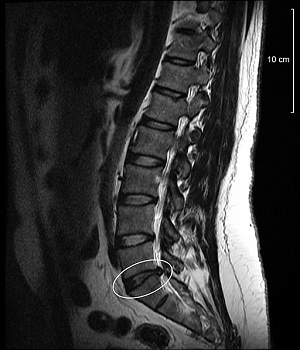

What Does a Bulging Disc Look Like?

Discs are like miniature jelly doughnuts, exactly the right size to fit between your vertebrae.

They’re made out of an outer layer of tough cartilage surrounding softer cartilage in the center.

A bulging disk looks like a hamburger that’s too big for the bun.

The disc extends outside its normal place, and the bulge typically affects a large portion of the disc.

Bulging is considered part of the normal aging process of the disk.

A herniated disk, on the other hand, happens when a crack in the tough outer layer of cartilage allows some of the softer inner cartilage to “escape” out of the disk.

Herniated disks are also called ruptured disks or slipped disks, and cause much more pain than compressed discs.

A bulging disc may not always cause symptoms, as the bulge does not necessarily compress nearby nerves.

Herniated discs, however, often result in more pain because the inner nucleus of the disc protrudes and can irritate or compress nerve roots.